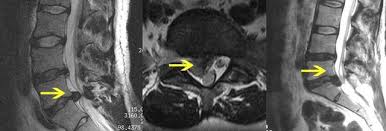

Bandscheiben op lws 4 5. Sie kommen meist zwischen den Wirbeln LWK Lendenwirbelkörper 45 und LWK 5SWK 1 Sakralwirbelkörper vor an der vorletzten und letzten Bandscheibe. Bandscheibenvorfälle sind Teil einer natürlichen Abnützung des Gewebes. Drückt der Gallertkern auf einen Rückenmarksnerven leiden Betroffene unter starken Rückenschmerzen die teilweise bis in Arme und Beine ausstrahlen.

Ursachen Diagnose und Therapie. Wie der Bandscheiben-Vorfall Prolaps ist die Bandscheiben-Vorwölbung Protrusion besonders häufig in der Etage bei L4L5 zwischen dem 4.

Wenn die Physiotherapie und Medikamente nicht mehr helfen und die Schmerzen zu stark sind oder wenn der Druck auf die Nerven Ausfälle verursacht Taubheit Muskelschwäche Lähmung sollte eine Operation in Betracht gezogen werden. Bandscheibenvorfall LWS Übungen - Hier findest du 5 effektive Übungen bei einem Bandscheibenvorfall in der Lendenwirbelsäule inkl. Es geht mir zur Zeit nicht gut mache mir auch große Sorgen wie es wird in den nächsten Tagen und Wochen mit den Schmerzen und Beschwerden. Ich wurde am 4. Frank aus München in. Probieren Sie es selbst aus. Sie kommen meist zwischen den Wirbeln LWK Lendenwirbelkörper 45 und LWK 5SWK 1 Sakralwirbelkörper vor an der vorletzten und letzten Bandscheibe. Die Bandscheiben der Wirbelsäule übt eine Art Stossdämpferfunktion aus und dient der Elastizität und der Beweglichkeit der Wirbelsäule. Lendenwirbel und dem 5.

Die Bandscheibenvorfälle an der Lendenwirbelsäule sind die häufigsten Bandscheibenvorfälle an der Wirbelsäule. In der Regel verschwinden die Schmerzen zwar nach der OP es kann aber immer sein dass sich Symptome nicht zurückbilden. Wenn die Physiotherapie und Medikamente nicht mehr helfen und die Schmerzen zu stark sind oder wenn der Druck auf die Nerven Ausfälle verursacht Taubheit Muskelschwäche Lähmung sollte eine Operation in Betracht gezogen werden. 3053 Beiträge ø047Tag Hallo vor 1 Woche hatte ich eine große Bandscheiben-OP. Wie der Bandscheiben-Vorfall Prolaps ist die Bandscheiben-Vorwölbung Protrusion besonders häufig in der Etage bei L4L5 zwischen dem 4. Bandscheibenvorfall 4-5 Lendenwirbel Hey S-A2011 danke für Deine Erzählung. Alleine in Deutschland werden jährlich ungefähr 150000 Bandscheibenvorfälle operativ behandelt.